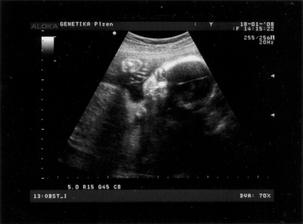

Náš svatební den byl 7.7.2007 a mimísek na sebe nenechal dlouho čekat 🙂 Už 21.8.2007 jsme na testu objevili // a těhu průkazku jsme dostali 12.10.2007. Naše bublinka by se měla narodit na konci dubna, tak uvidíme, kdy se jí bude chtít na svět.